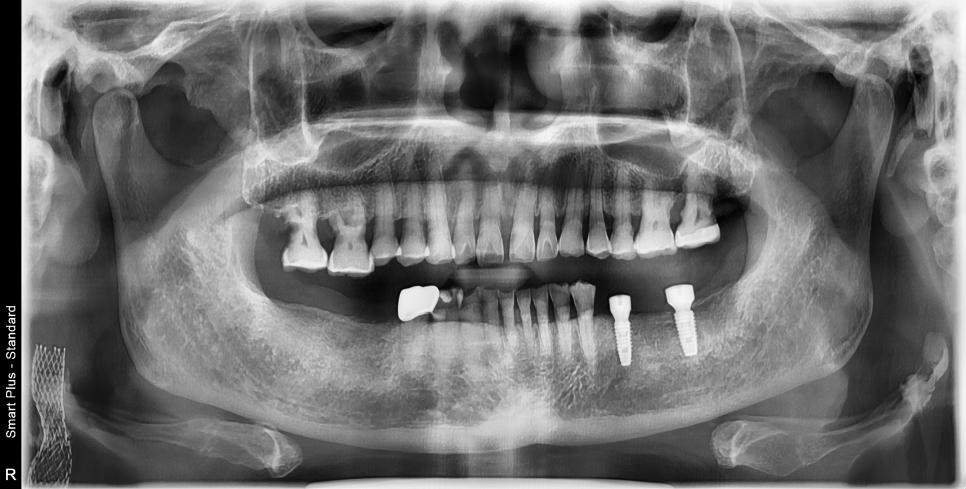

문진-파노라마촬영-ct촬영-임플란트식립-지대치연결-보철물연결

단순한임플란트과정은이렇습니다.

만약잇몸뼈가부실하다면 신논현역치과 임플란트 잘하는 스마일뷰치과에서는

임플란트식립전에 뼈이식을 진행하게 되는데